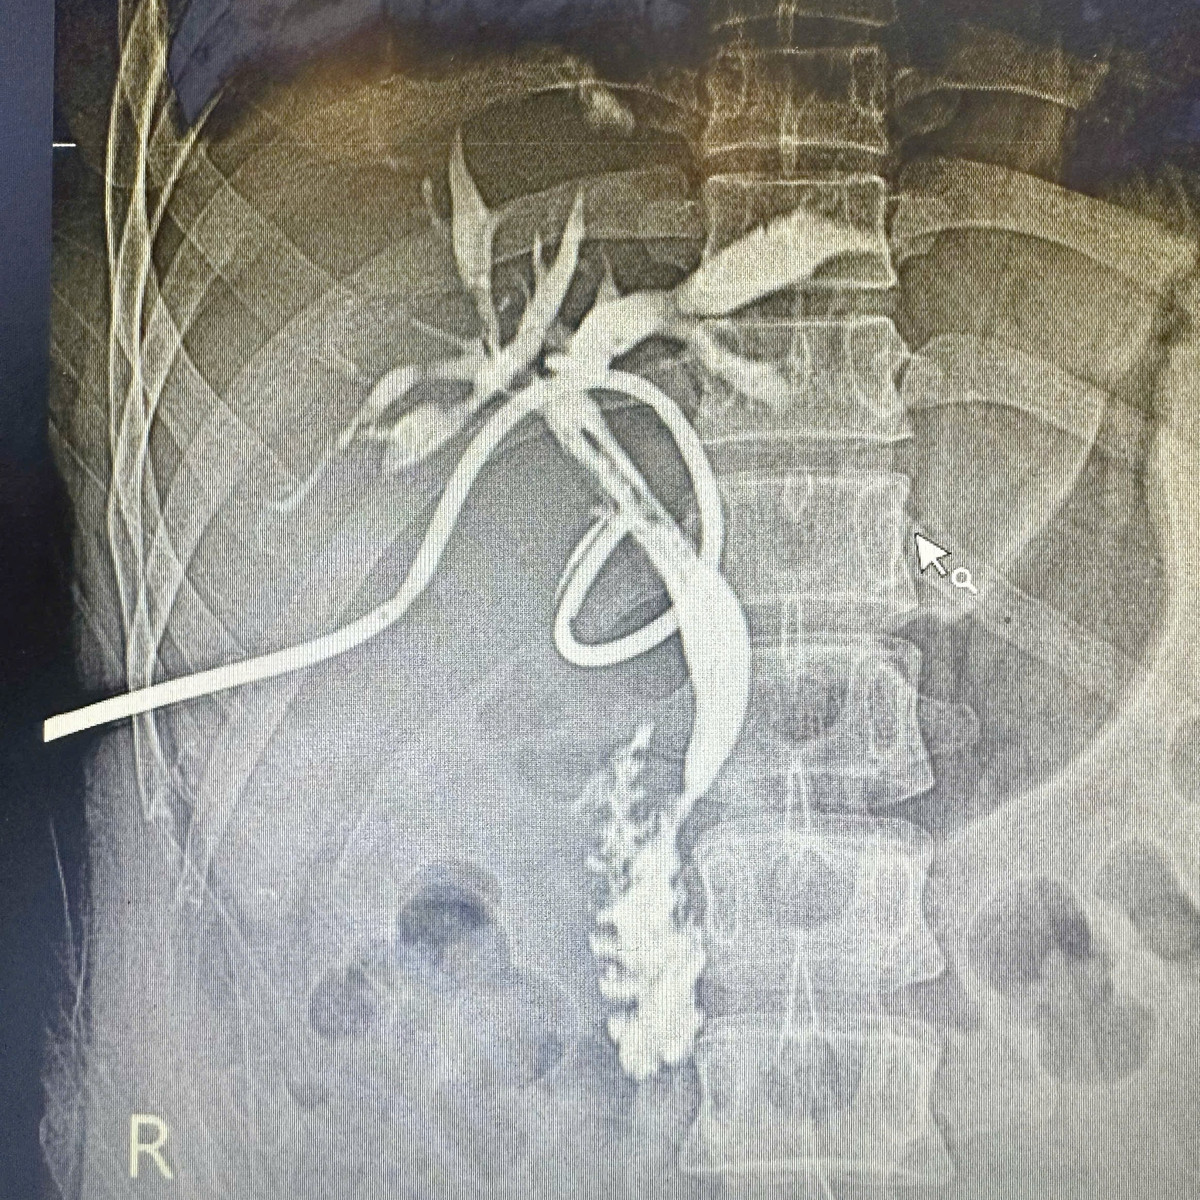

Trong quá trình phẫu thuật, thông qua hệ thống nội soi đường mật ống mềm, các bác sĩ đã tiếp cận các nhánh đường mật trong gan, xác định vị trí sỏi và tiến hành tán sỏi bằng laser, sau đó lấy hết các mảnh sỏi ra khỏi đường mật. Kết quả chụp kiểm tra sau mổ cho thấy hệ thống đường mật lưu thông tốt, sạch sỏi.

Phim chụp kehr sau mổ cho thấy đường mật đẹp, sạch sỏi - Ảnh BVCC